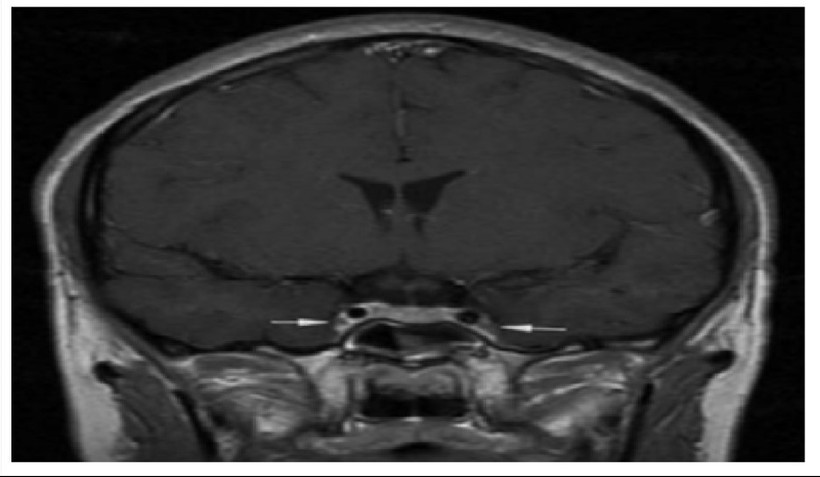

Vị trí mũi tên là viêm và co thắt động mạch cảnh trong 2 bên.

Theo hồ sơ bệnh án, bệnh nhân khởi phát bằng viêm xoang cấp mủ, sau đó chuyển sang viêm tấy nửa mặt, rồi nhanh chóng xuất hiện rối loạn ý thức và co giật. Kết quả chụp cộng hưởng từ sọ não cho thấy bệnh nhân có phù nề lan tỏa, dấu hiệu điển hình của viêm tắc tĩnh mạch xoang hang - một tình trạng huyết khối nhiễm trùng ở nền sọ.